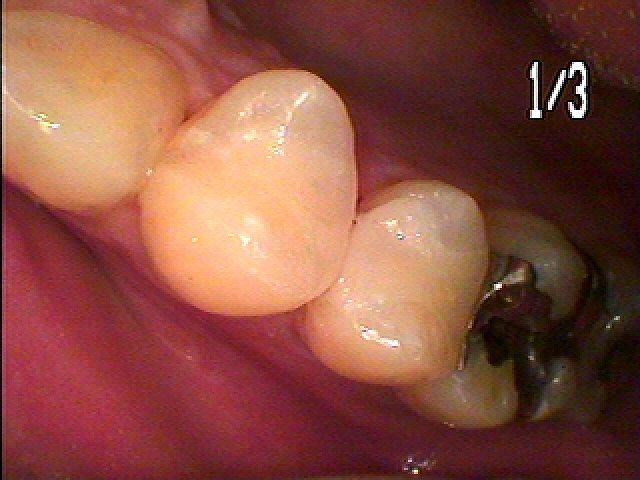

右下の6番部

CR樹脂の下が黒く虫歯になっています